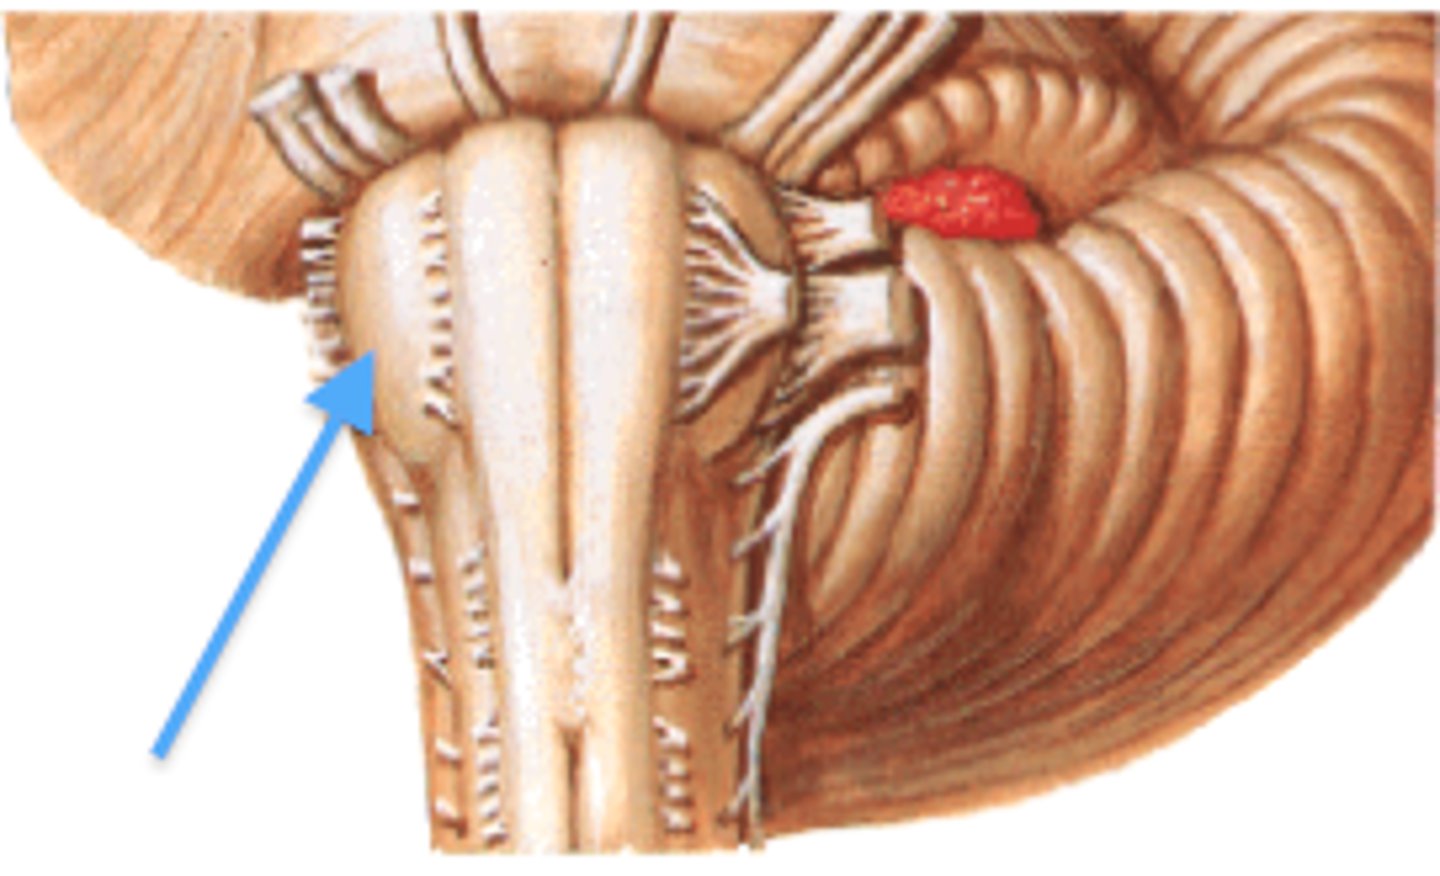

2nd largest, crescent-shaped, separates cerebrum (occipital lobes) from cerebellum (arrow #5)

falx cerebelli

seperates the two hemispheres of the cerebellum. it lies inferior to the tentorium cerebelli, separating cerebellar hemispheres (arrow #7)